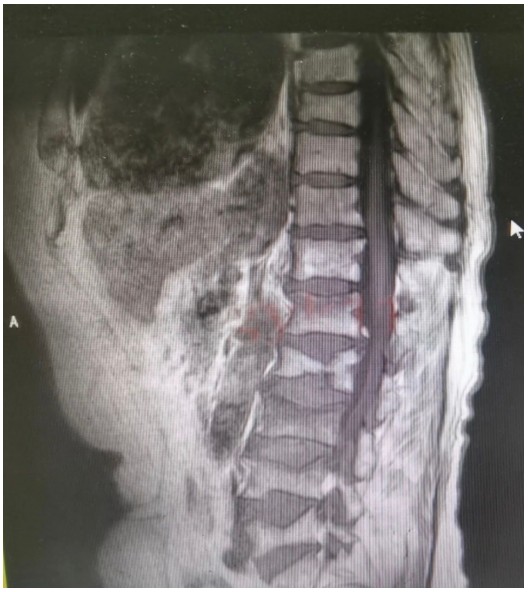

原來,89歲的占大爺因在家勞作時突發(fā)腰背部疼痛難忍、腰部無法直立,行走困難,在家臥床休息兩周后疼痛仍未減輕,于是來到衡陽市中心醫(yī)院脊柱外科就診。接診的盛凱醫(yī)師仔細(xì)查體結(jié)合磁共振檢查發(fā)現(xiàn),占大爺腰椎L1、L3、L4有椎體壓縮骨折,診斷為腰椎體壓縮骨折、重度骨質(zhì)疏松癥。錢軍博士團(tuán)隊結(jié)合對病人多椎體的骨折做出了細(xì)致的評估,經(jīng)過認(rèn)真分析研究,決定為患者實施腰椎體壓縮性骨折經(jīng)皮穿刺椎體成形術(shù)(PVP)。手術(shù)當(dāng)天,醫(yī)師團(tuán)隊在C-臂監(jiān)視器透視下,分別定位L1、L3、L4雙側(cè)椎弓根位置,以標(biāo)記穿刺點(diǎn)為中心做3mm切開,在透視下注入骨水泥,再次透視見骨水泥位置良好,順利完成手術(shù)。